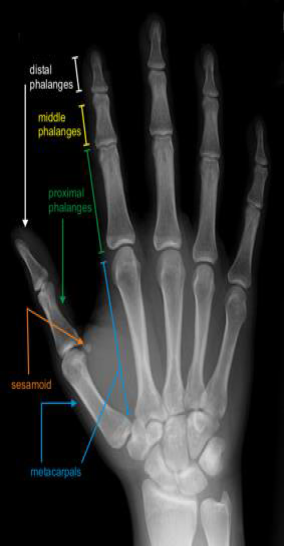

CARPAL Fractures and dislocations Facts Fractures and dislocations involving the carpus can be easily misdiag…

2729 DEFINITION ■ The finger metacarpophalangeal joint (MCP joint) is com- monly and characteristically invol…